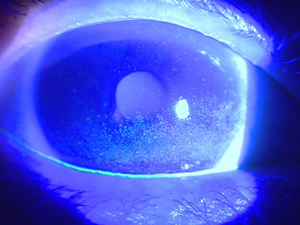

アレルギー性結膜炎

目の表面に花粉などのアレルゲン(アレルギー反応を引き起こす物質)が付着して、結膜に炎症を起こす病気です。

結膜とは、まぶたの裏側と白目の部分を覆っている粘膜のことです。

| 主な症状 |

はやり目

(流行性結膜炎・咽頭結膜熱)

アデノウイルスという非常に感染力の強いウイルスが原因でおこる結膜炎です。

潜伏期間は1~2週間あり、感染経路は手などを介した接触感染によりうつります。